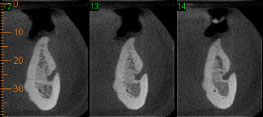

CASO 6 - Reabsorção

Achado radiográfico, na radiografia periapical de rotina, nota-se área de menor densidade na distal cervical e alteração no contorno na mesial, e rarefação óssea periapical. Ao exame tomográfico pode-se observar o dente 11 com osteólise apical e área de reabsorção na distal e reabsorção por substituição na mesial.